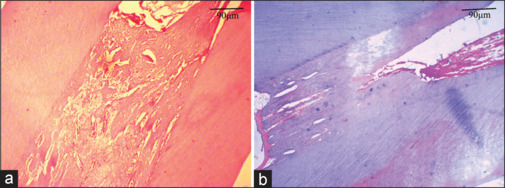

Materials and methods: In this experimental study, a total of 12 immature mandibular central incisors from six adult male sheep, weighing 30-40 kg and with the age of 1 year old with Merino race were examined. After anesthesia, the pulps of the teeth in the case group were mechanically exposed and then were restored with reinforced zinc oxide-eugenol and amalgam. In the control group, the teeth remained intact. The animals were sacrificed at intervals of 2, 4, 6, and 8 weeks (E2, E4, E6, and E8) in the case and 2 and 8 weeks (C2 and C8) in the control groups. Then, their teeth were removed with the surrounding supporting tissues and alveolar bones. Tissue processing and staining were done, and the sections were examined under a light microscope. The Kruskal-Wallis and Mann-Whitney U tests were used to analyze the data and compare the changes between the two groups. P < 0.05 was considered statistically significant.

Results: In response to mechanical exposure, reparative or tertiary dentin was formed, and its thickness increased during the time of the study. The thickness of the odontoblastic layer in the E4 group was the highest amount. The pulp chamber diameter in the C2 group was significantly larger than the other groups, and the diameter of the apical foramen in the E8 was decreased significantly compared to the controls (P < 0.05).